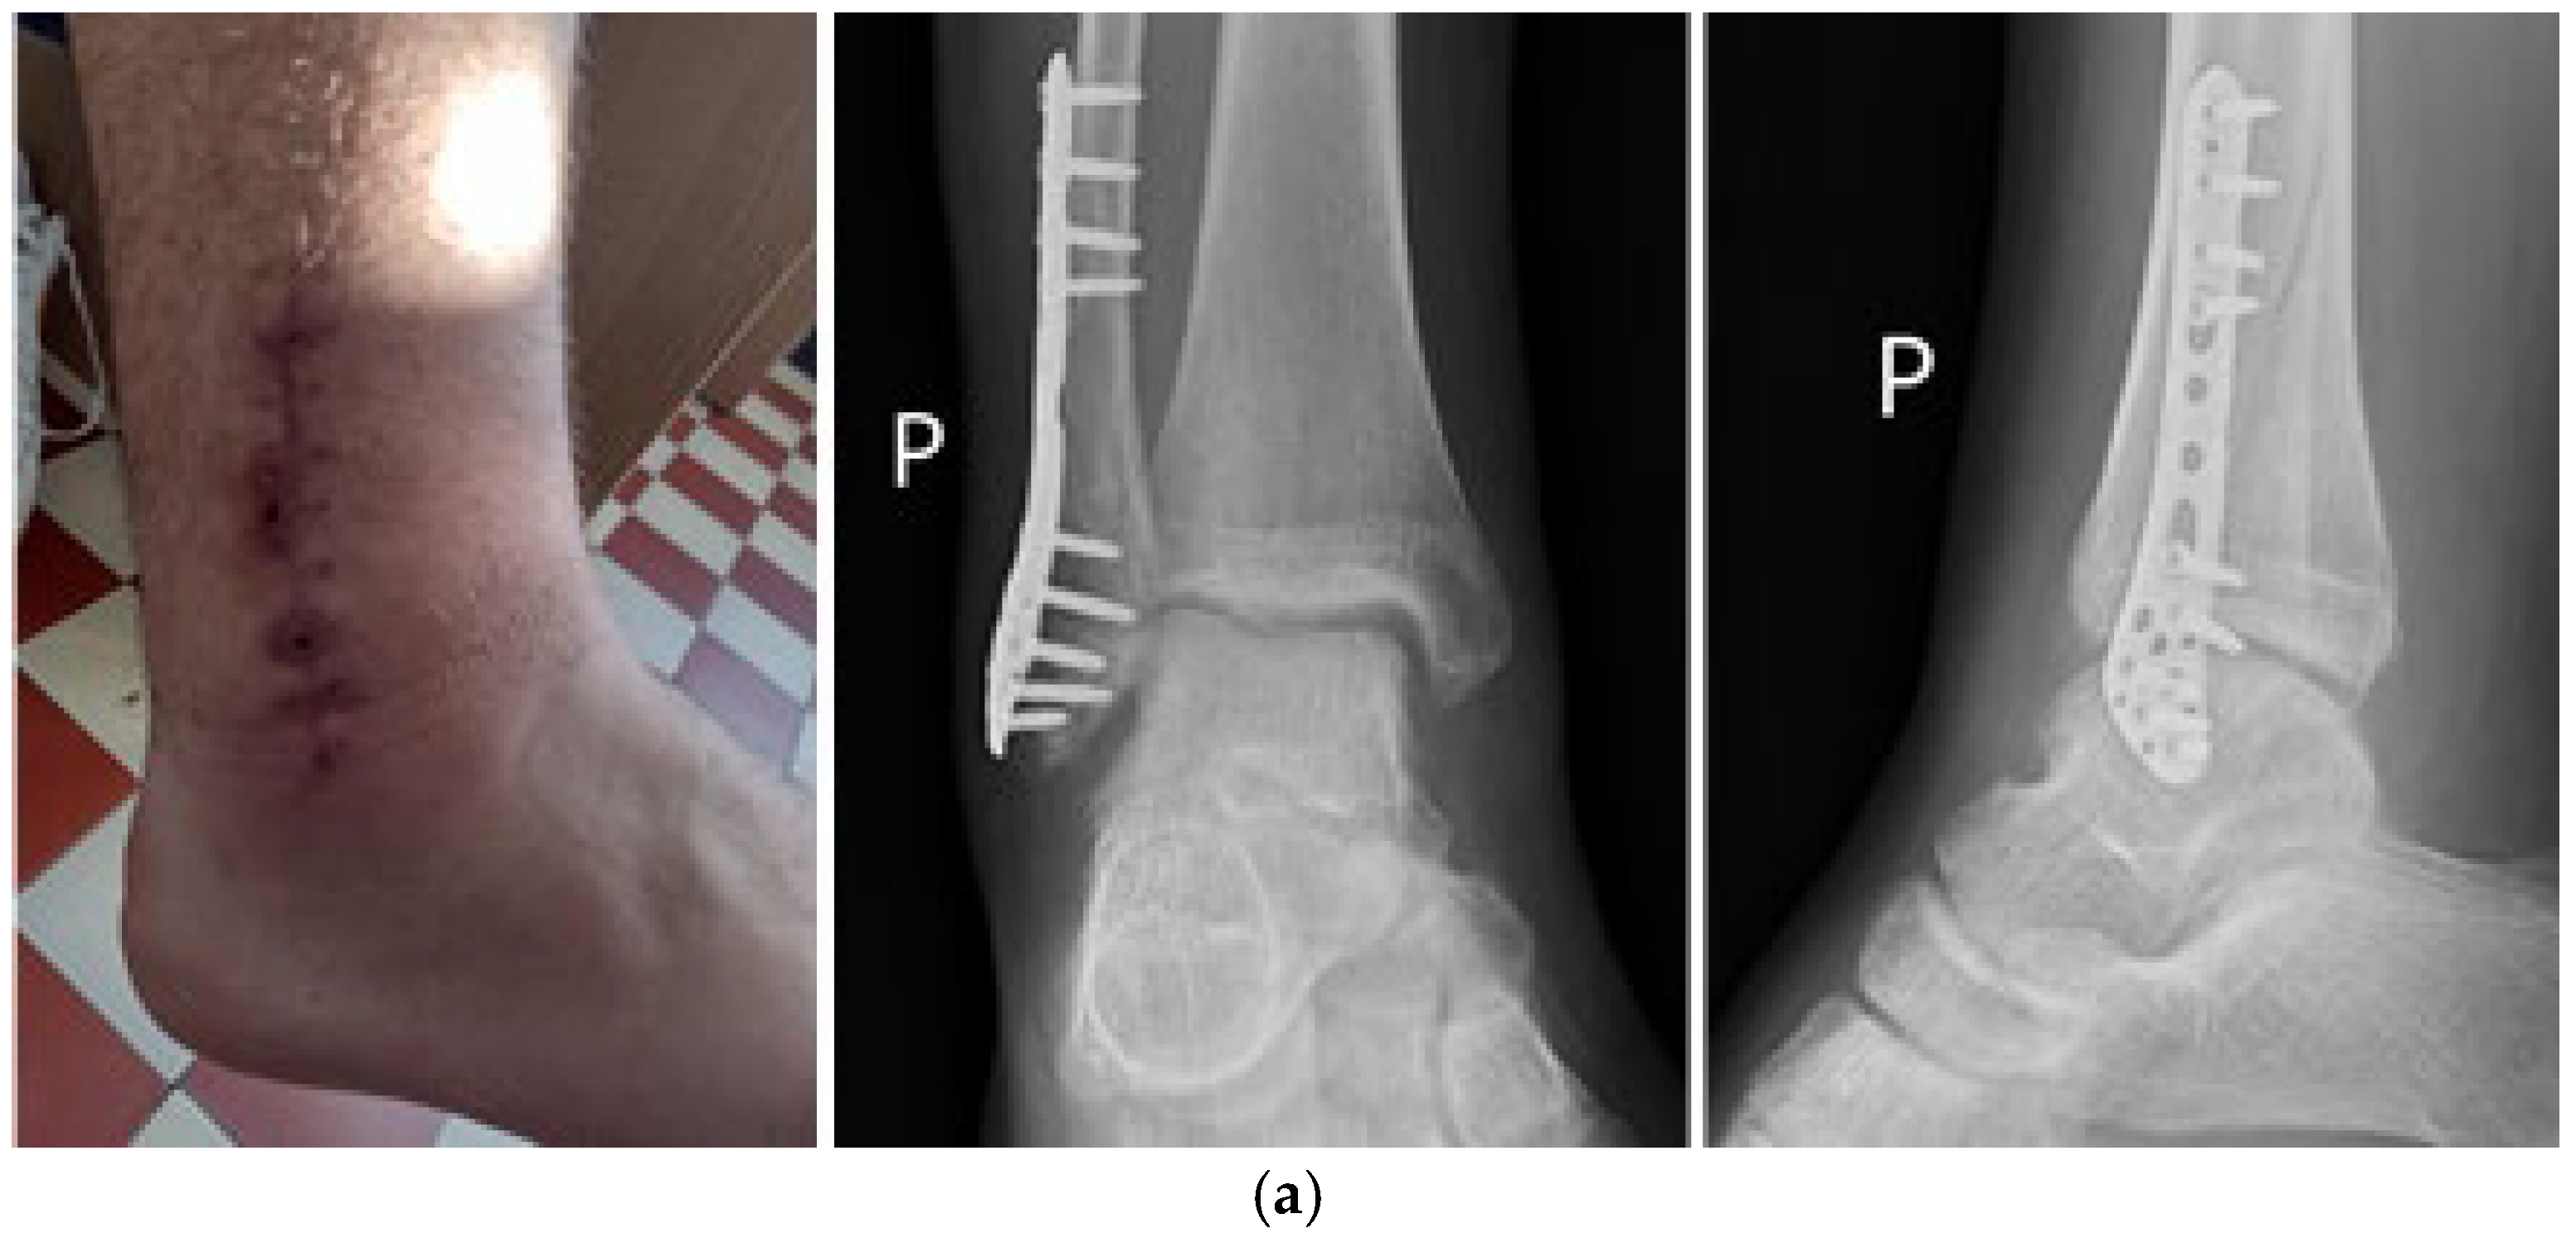

7. Macroscopic Observations of Interacted Surfaces of Removed Implants—Author Observations